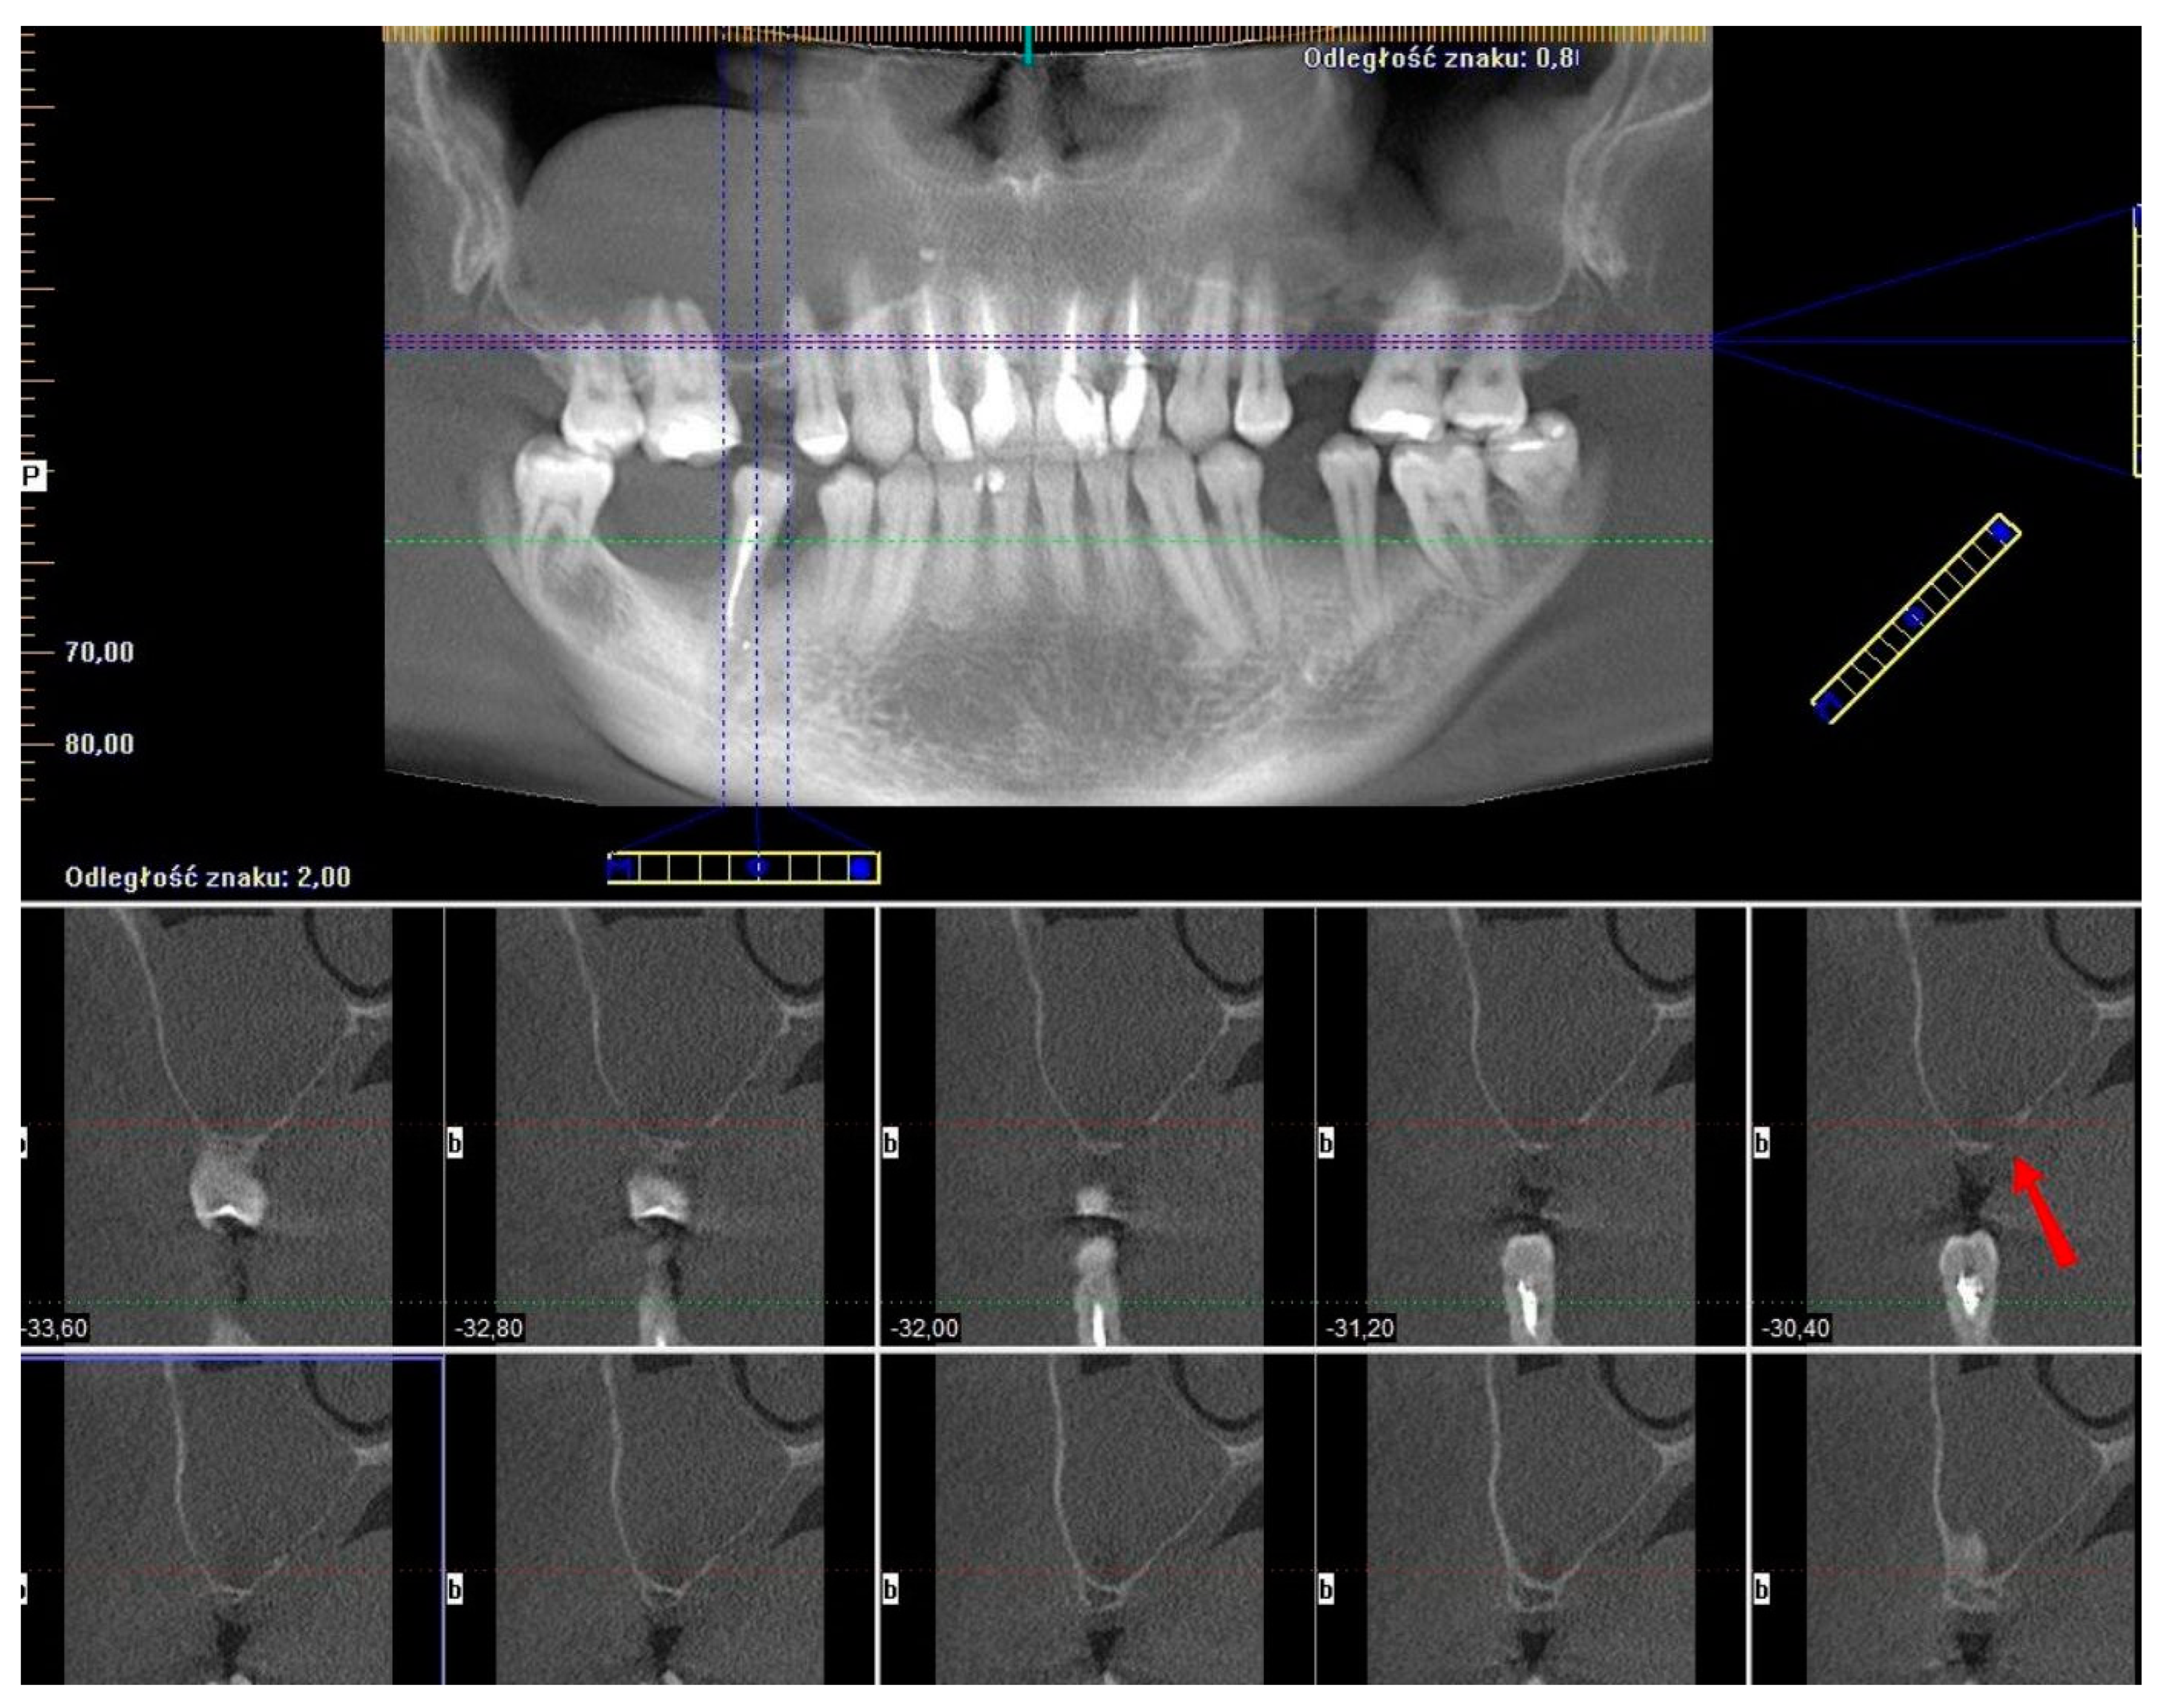

2.1. Case 1—Primary Version

This case sets a proper example of the primary version of the CET that has been conducted on a patient qualified for open sinus lift before implant placement in positions 16 and 15 (FDI numbering system) (Figure 1A,B). CBCT unveiled a homogeneous “dome-shaped”/“rising sun” solitary radiopaque mass located at the floor of the right maxillary sinus, precisely above the region of the planned sinus lift (Figure 1C). The radiological image, class III B by Di Girolamo classification [6], combined with the absence of symptoms, suggested a mucous retention cyst or pseudocyst of the maxillary antrum [2]. Although in such cases, Di Girolamo et al. suggest endonasal sinus surgery (ESS) before sinus lift due to possible difficulty in sinus floor elevation and risk of ostium obstruction, our article provides a solution to avoid ESS and prolonged treatment without compromising the sinus lift procedure and the final outcome.

Figure 1. Clinical situation before the surgery. Occlusal view (A), lateral view (B), and CBCT scans with a dome-shaped radiopaque lesion in the sinus and insufficient bone height that requires sinus lift before placing implants (C).